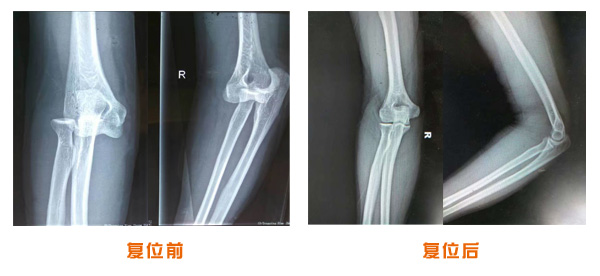

肘關節脫位骨折治療前后對比

踝關節脫位骨折治療前后對比